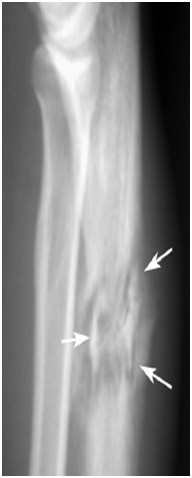

Acute osteomyelitis imaging characteristics: 15

Radiographs

Radiographic findings of acute osteomyelitis are typically not present for 7 to 14 days following the onset of infection.

The early radiographic manifestations of osteomyelitis consist of:

Permeative osteolysis

Endosteal erosions

Intracortical fissuring

Periostitis.

Differential diagnosis: Ewing sarcoma, aggressive neoplasm or Stress fracture (Figure 10).

Figure 10 Plain x-ray of the ankle in a case of osteomyelitis showing permeative osteolysis.